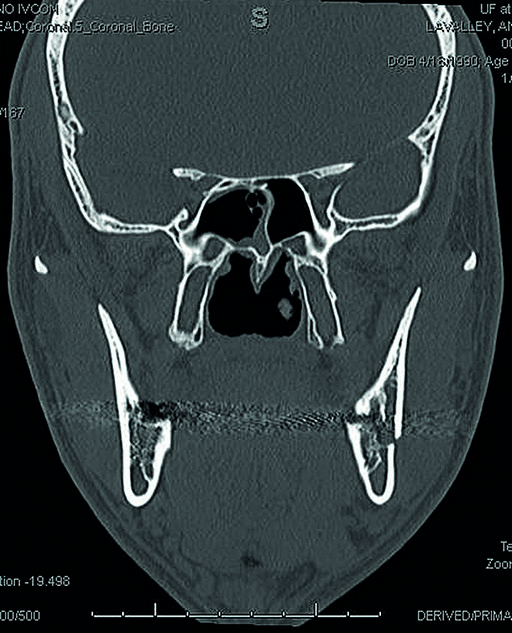

A 28 year old white male was subject to personal assault, and sustained a left mandibular angle fracture (Fig 1). The fracture was prestabilized with the Matrix Wave system and then fixated with a 4-hole miniplate 2.0 on the superior border and a 4-hole angulated universal fracture plate 2.4 along the inferior border. A pre-existing anterior open bite was noted and confirmed with the patient prior to presentation to the operating arena.

The MatrixWAVE plate was attached to the maxilla with screw placement in the inter-root spaces (Fig 2). A second MatrixWAVE plate was attached in corresponding position to the mandible, with screw placement in the inter-root spaces (Fig 3). Wires were placed around the plate hooks to bring the dental arches into occlusion. Note the preexisting anterior open bite (Fig 4). Careful adjustment of the MatrixWAVE plate and wiring in the region of the mandibular fracture allowed the bone fragments to be precisely aligned without the requirement for screw repositioning (Fig 5). The postoperative panoramic x-ray (Fig 6) shows the two MatrixWAVE plates in situ, with other plates used to fixate the left mandibular angle fracture. Note that a portion of the Matrix- WAVE plate was removed from the left molar region in the mandible (Fig 6).